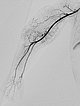

Digitale Subtraktionsangiographie nach Beginn der Embolisation mit Ethylen-Vinyl-Alkohol-Kopolymer über einen Mikrokatheter mit ablösbarer Spitze. Gleichzeitig Entnahme einer Stanzbiopsie zur histologischen Untersuchung.